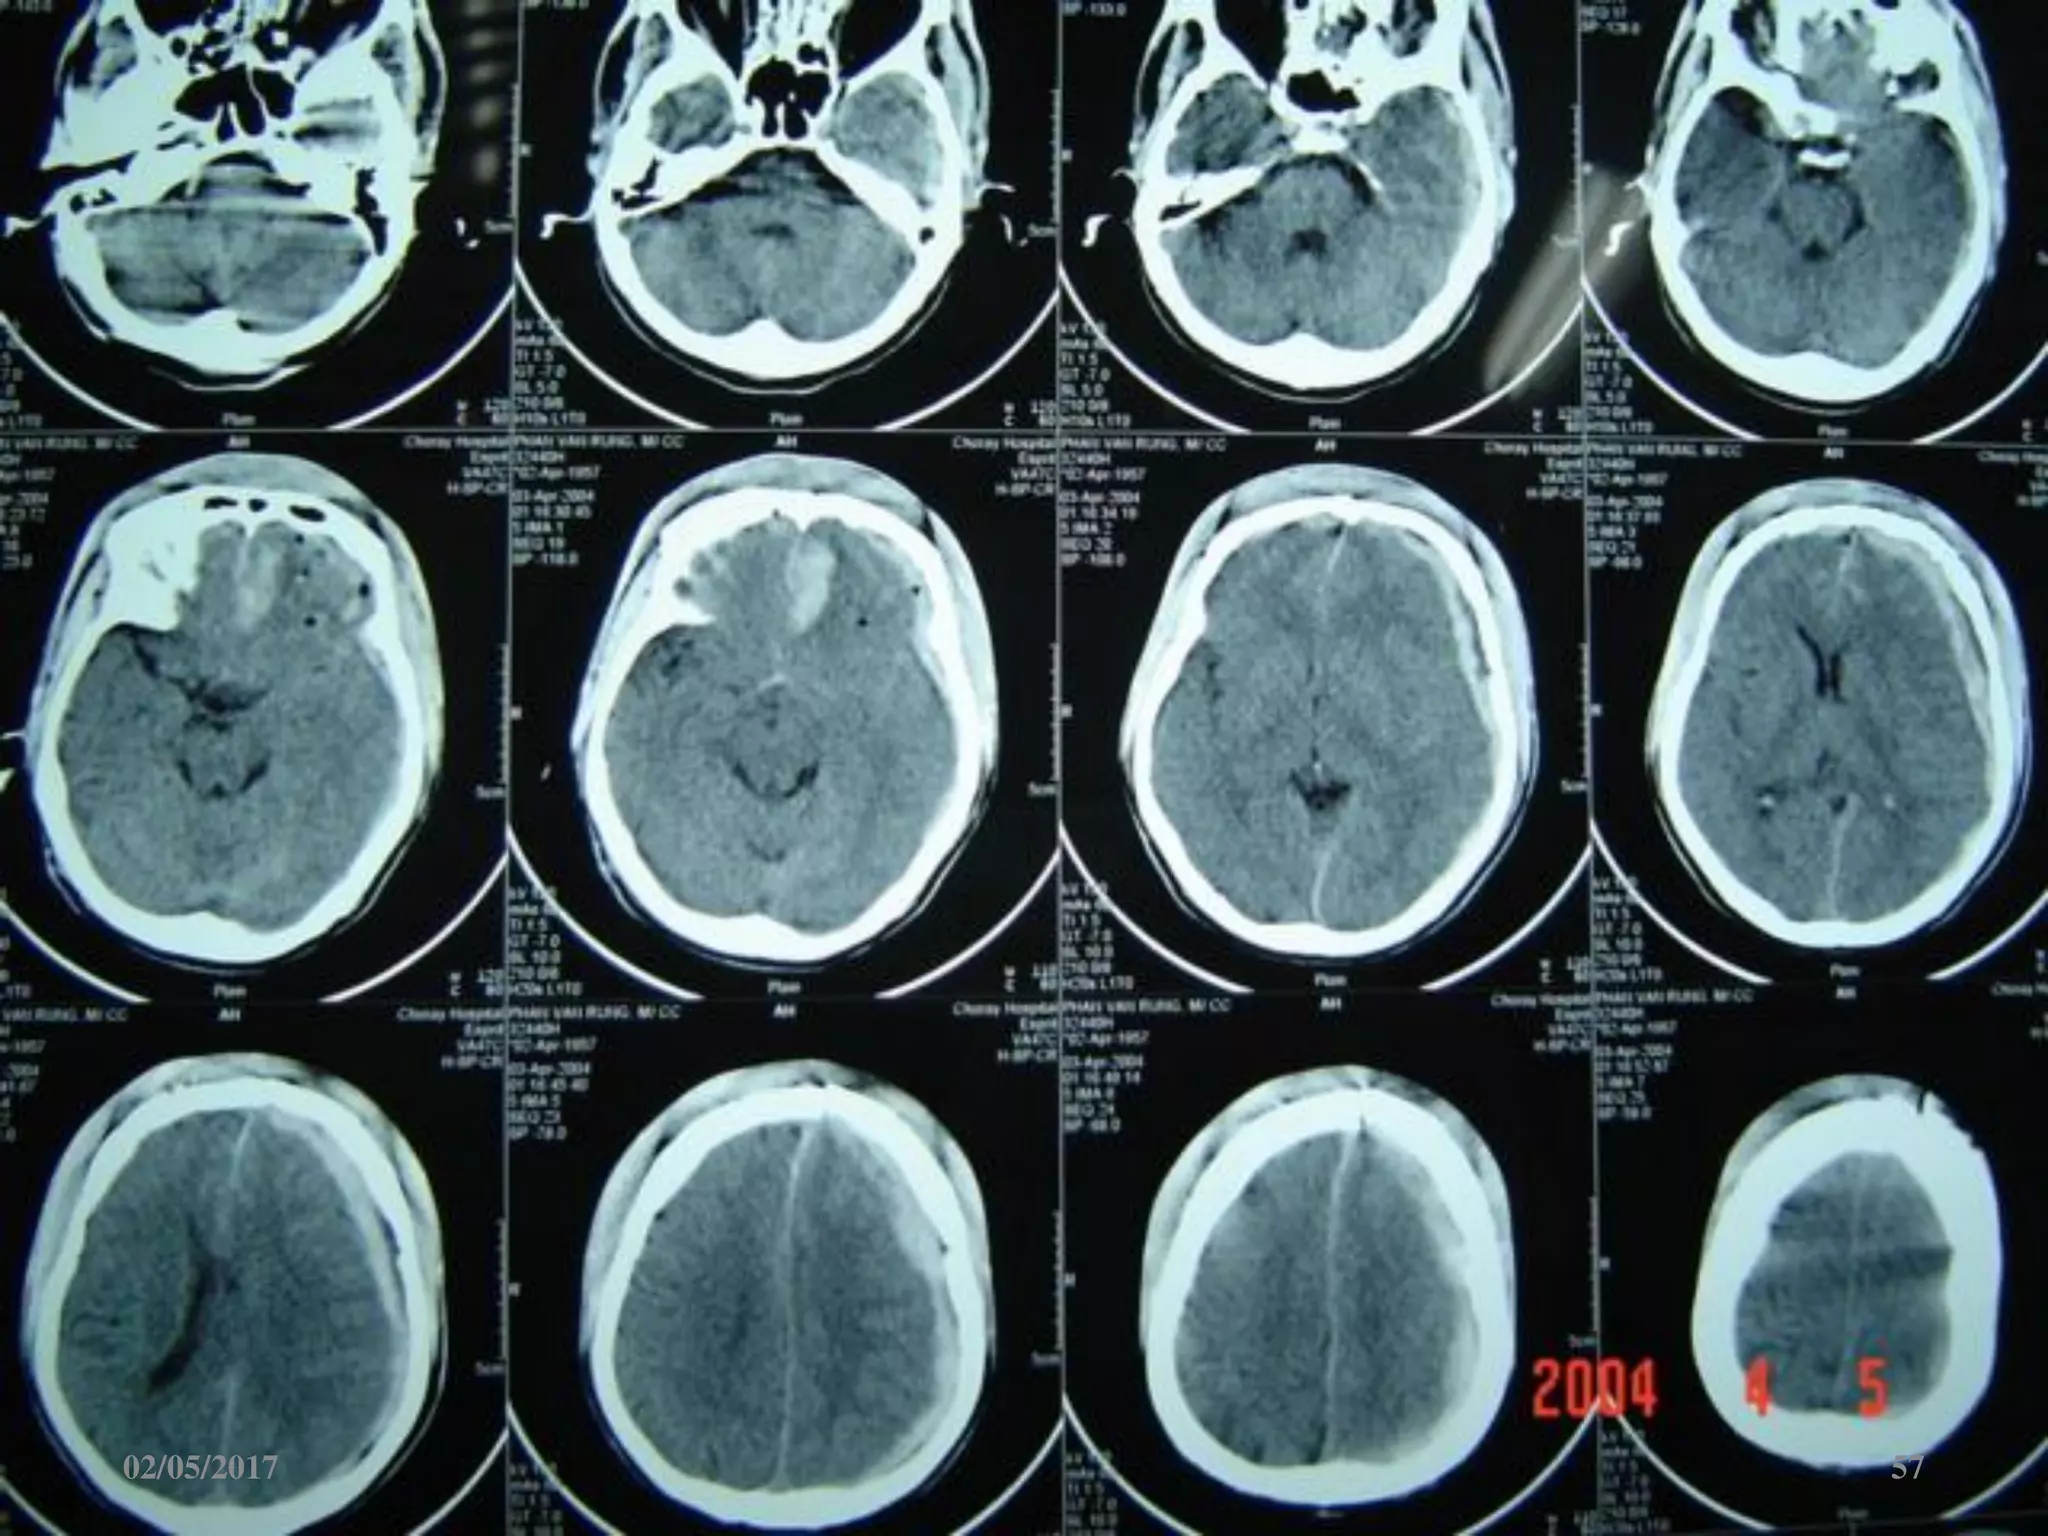

Máu tụ dưới màng cứng cấp

 Ngoài trục, hình liềm,

tăng đậm độ

 Vượt qua được các

khớp sọ

 Thường kèm dập não

02/05/2017 57